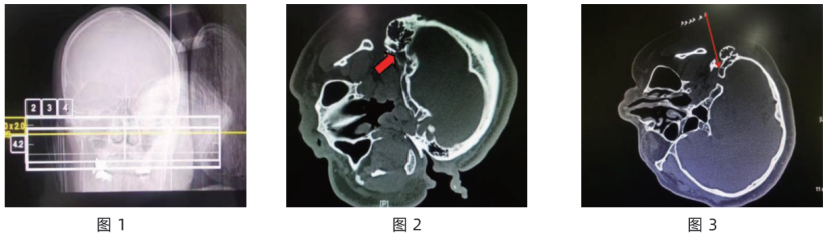

射频热凝过程中,为了观察病人面部肌肉跳动情况未给予麻醉药,术前常规给予镇痛药物。病人进入CT室,患面朝上侧卧于检查床,头下垫薄枕,常规吸氧、监测生命体征,于耳垂下方平行于下颌线斜行放置定位栅。以CT鼻旁窦模式轴位扫描(见图1),以层厚3 mm对乳突区进行轴位扫描,逐层影像寻找茎突、乳突解剖结构,并由末端向头端逐层寻找至两者根部汇聚成的类圆形孔洞结构,即茎乳孔(见图2)。

图1 CT 引导下茎乳孔面神经射频治疗面肌痉挛乳突区轴位扫描图(病人侧卧位,放置定位栅,斜行放置于耳垂下后方)

图2 CT 引导下乳突前入路经茎乳孔面神经穿刺到达靶点示意图(红色箭头所指为穿刺针位于茎乳孔处)

图3 CT 引导下乳突前入路经茎乳孔面神经穿刺层面、穿刺路径设计图(红色箭头表示穿刺路径及方向)

择含茎乳孔层面作为目标靶点层面,测量并标注出穿刺角度和深度,设计好进针路径及方向,标记定位线,常规消毒、铺单、戴无菌手套,穿刺点行1%利多卡因局部麻醉,用射频套管针(北琪医疗科技有限公司,22G/100 mm/5 mm)穿刺,全程以层厚2 mm CT扫描,直至确认针尖到达茎乳孔外口处(见图 3),连接射频仪(北琪医疗科技有限公司,R-2000BA1),行感觉测试 (50 Hz、0.6 mA) 可诱发出面部以疼痛感,再行运动测试(2 Hz、0.6 mA)以电压由0开始每0.1 V 逐渐升高,直至诱发出患侧面部肌肉节律性抽动,记录此时电压,确认针尖位置准确。